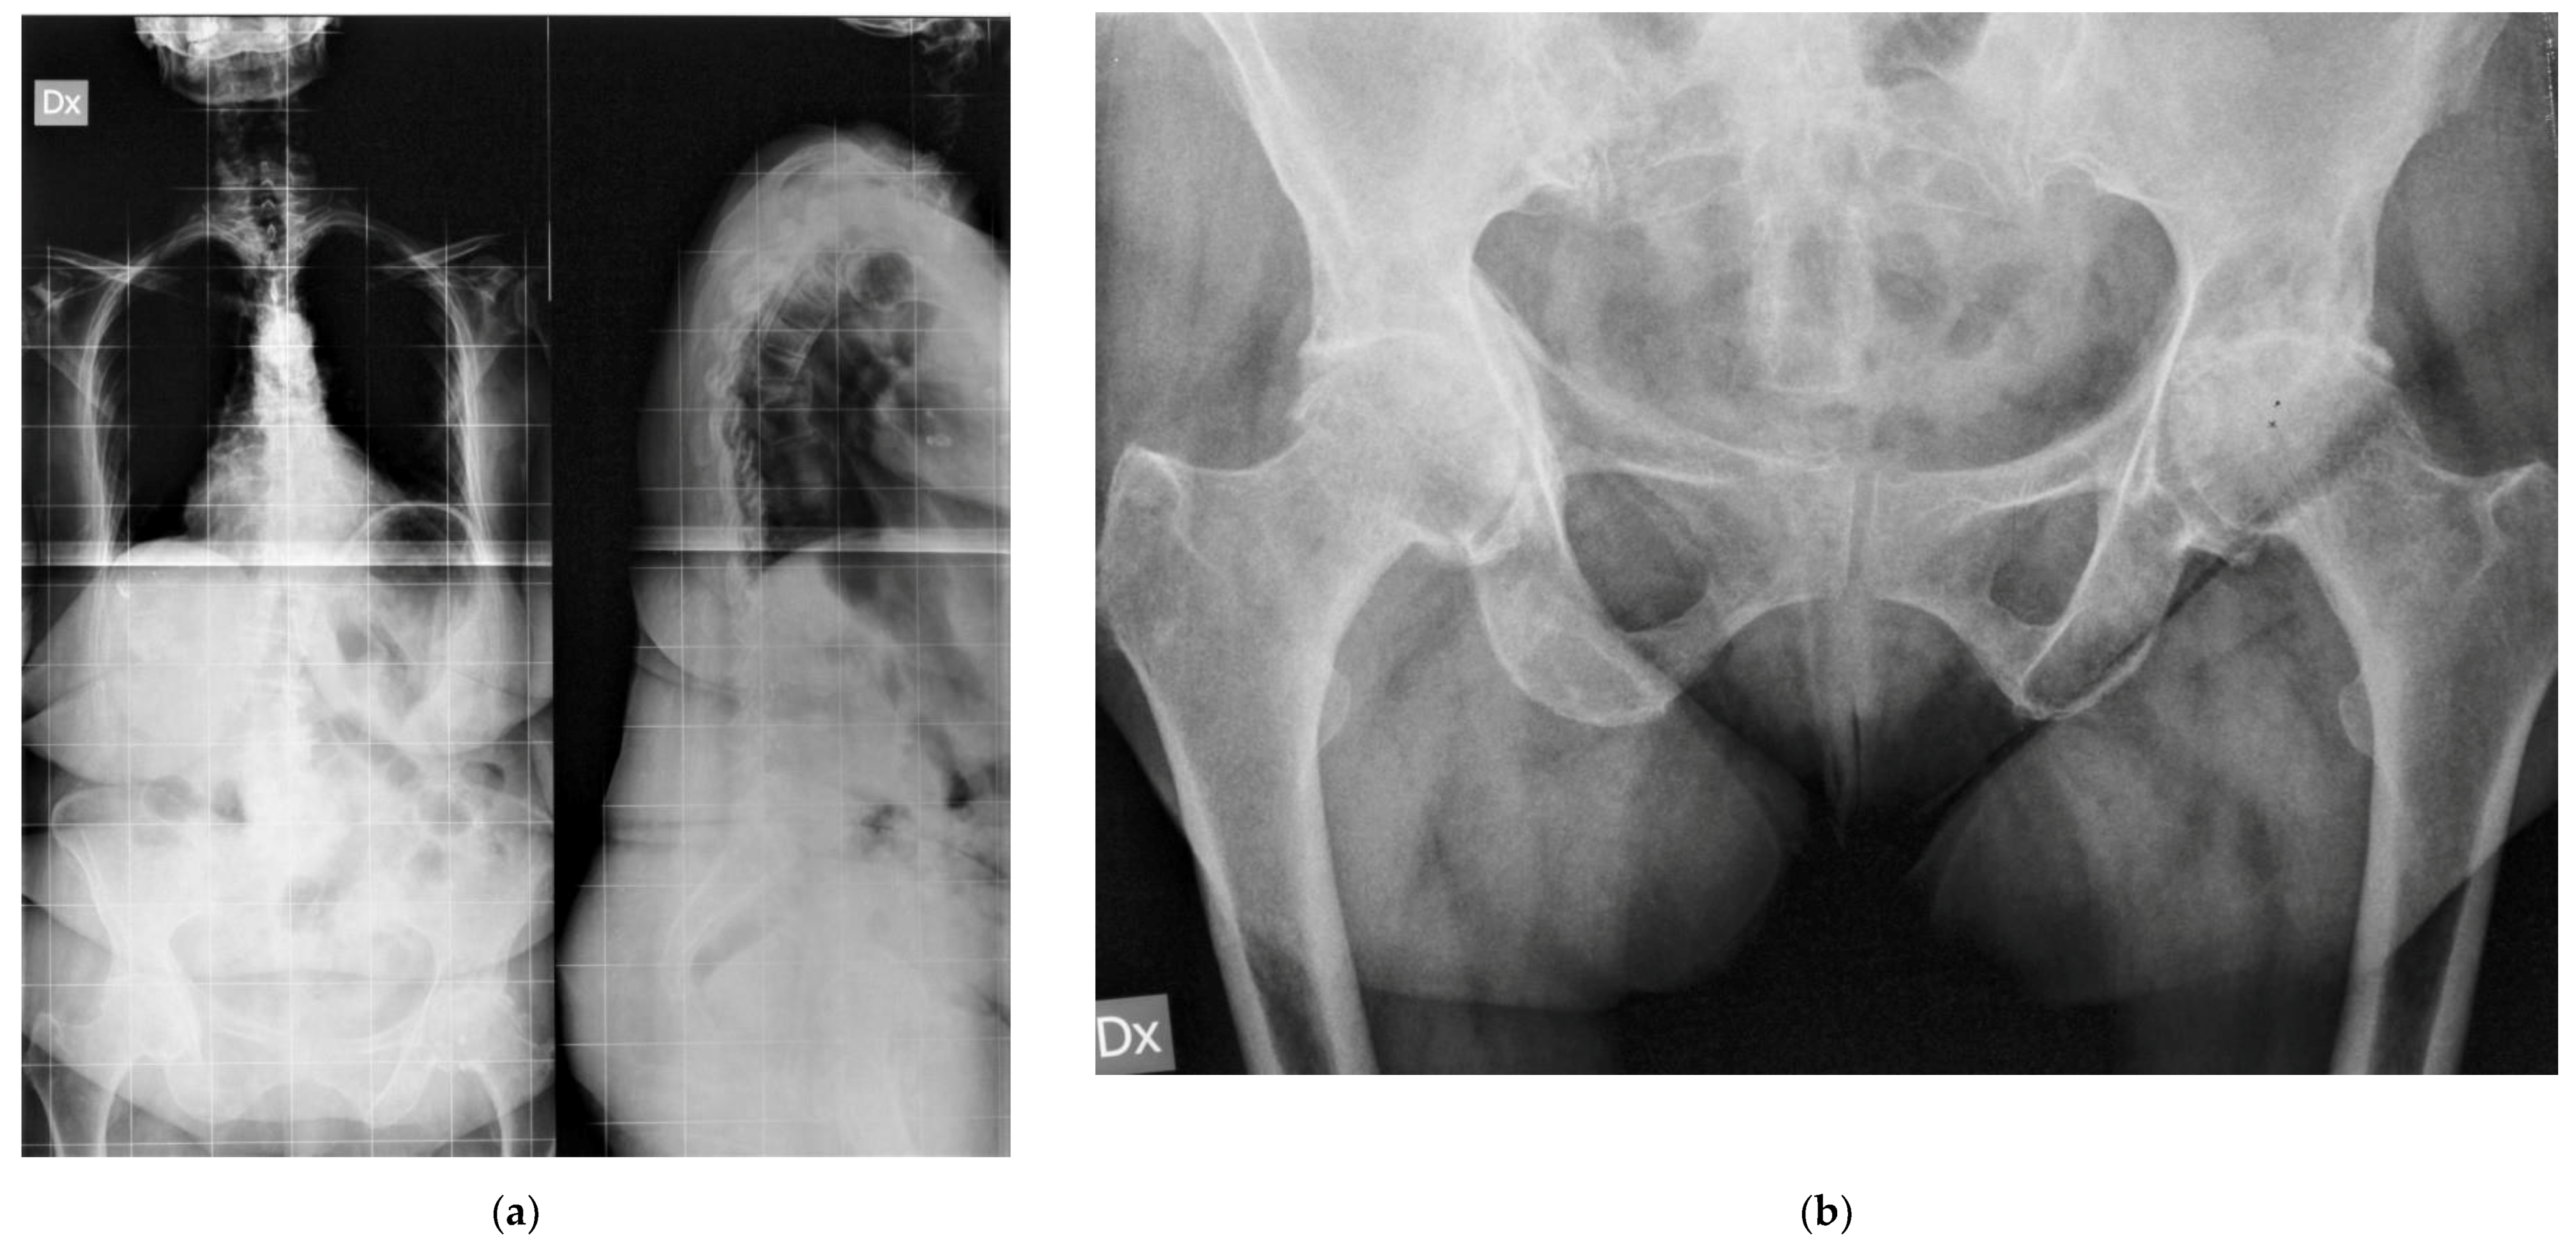

Figure 3 shows the case of a 68 years old female, who was referred to our unit due to persistent low back pain for vertebral steno-instability and consequent sagittal imbalance to undergo spinal lumbo-sacral fusion; clinical and radiological examinations revealed a concomitant severe osteoarthritis in both her hips that was treated with bilateral THA with the G7 modular cementless DM cup. After surgical treatment in the hips, low back pain improved dramatically, and the patient did not need any surgery in her spine.

Figure 3. steno-instability and consequent sagittal imbalance oh the spine (a); severe bilateral hip osteoarthritis (b); staged bilateral total hip replacements using DM modular cups and cementless stems (c).